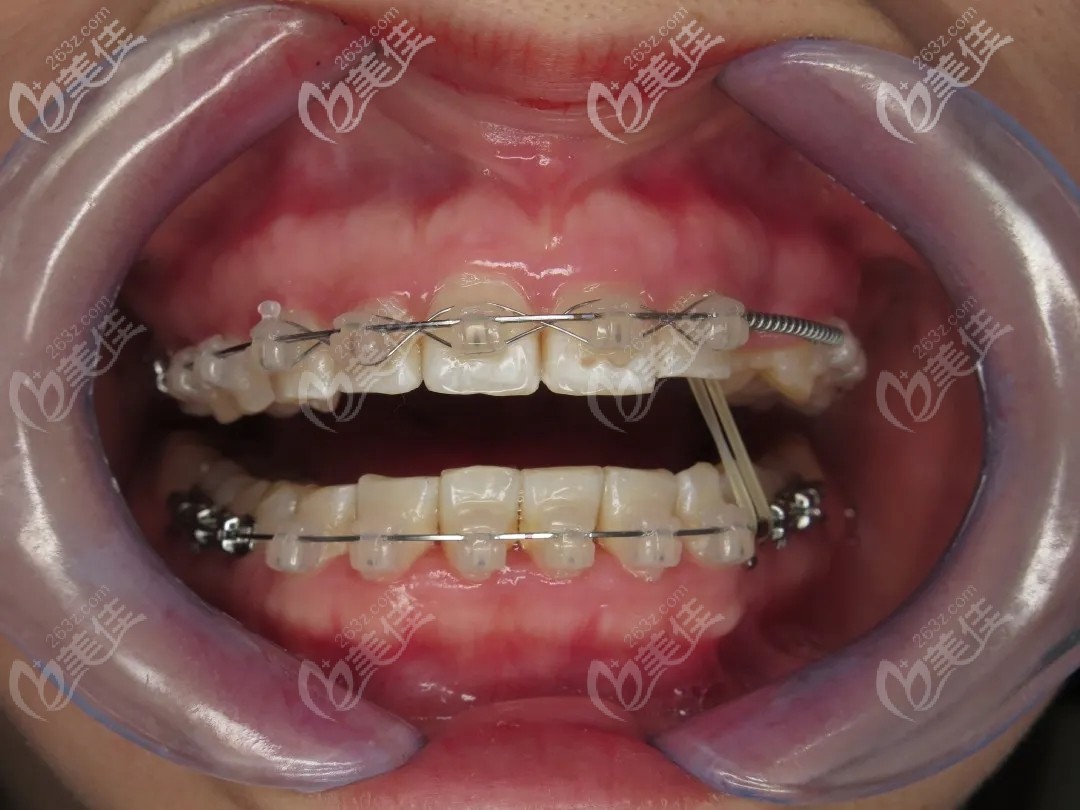

經(jīng)過內(nèi)心一通“打架”后,她選擇了陶瓷冰晶自鎖牙套,比全隱形牙套價(jià)格便宜,比傳統(tǒng)金屬牙套好看點(diǎn)。

終于在矯正滿1年的時(shí)候,藏匿的歪牙冒出了小頭,兩個(gè)月時(shí)間就長出了大半截,當(dāng)時(shí)簡(jiǎn)直高興的不得了。

2020年11月28日,長達(dá)兩年的矯牙之路終于畢業(yè)啦!矯正后,小仙女終于重拾“吃貨的希望”。